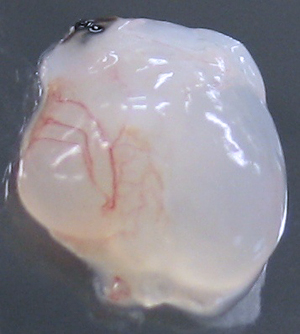

A heart with visible blood vessels and newly-formed tissues obtained by seeding a heart scaffold with stem cells

© IBN 2012